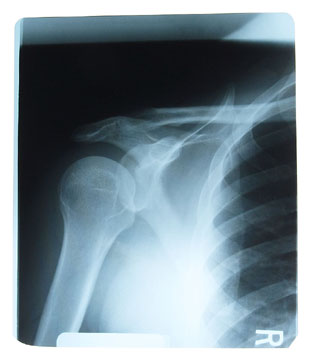

Frozen shoulder or adhesive capsulitis.

Is a condition which affects shoulder joint mobility with stiffness and pain and occurs usually between the ages of 40 and 60. Unaided recovery can be slow and symptoms can last for two to three years.

Diagnosis

The chiropractor will be able to make an accurate diagnosis using orthopaedic and neurological tests and may suggest referral for diagnostic x-rays.